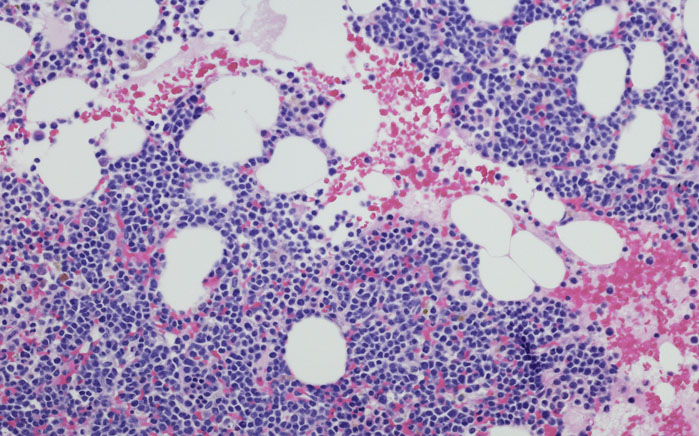

Son las células plasmáticas de la sangre (encargadas de la formación de las inmunoglobulinas o proteínas que nos defienden de las infecciones) las que se alteran e inician un crecimiento descontrolado. Este crecimiento celular anormal tiene lugar en la médula ósea, que como su nombre indica está en el interior de los huesos, y así se pueden formar múltiples tumores de células de tipo mieloide, y de ahí viene su nombre.